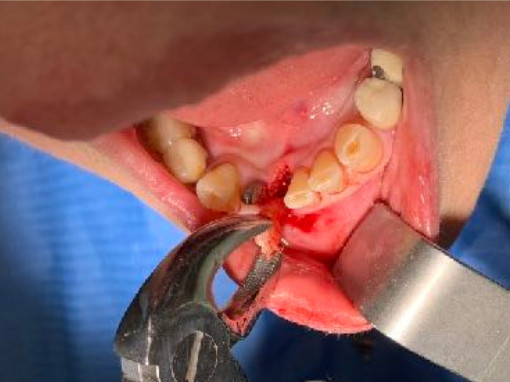

Situaz.estrattiva

postestrattivo immediato

Sequenza frese

solo lanceolata

No maschiatore

Carico occlusale

Immediato in leggera occlusione

Complicanze